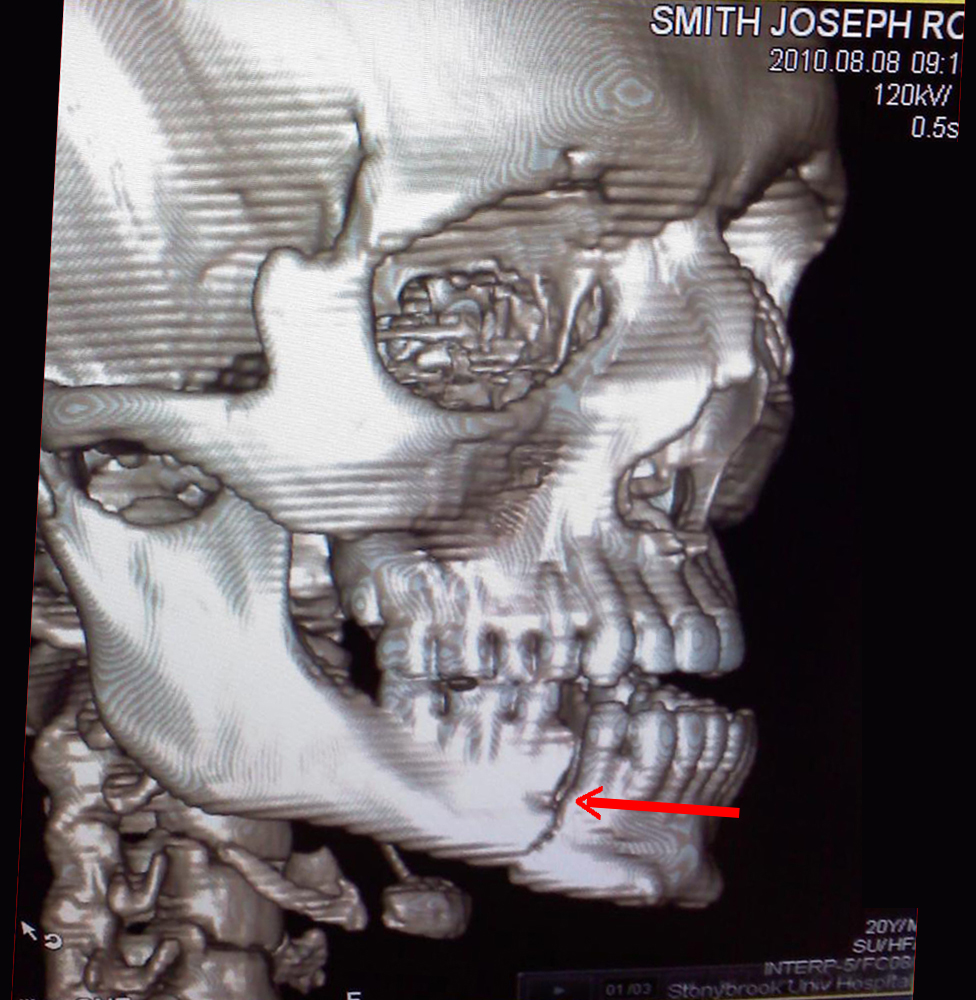

Smith suffered two severe fractures to his jaw in the last thirty seconds of round two against then displaying more courage and heart than almost anyone not carrying an M-16. The young boxer puncher went on to fight and in my opinion win almost six minutes before succumbing to the pain.

It wasn’t until about the 2:50 mark of round four when during a clinch Caminero fired off some in close rabbit style punches in close that Smith succumbed to the pain of what would later be diagnosed as double fractured jaw. Pulling out of the clinch Smith turned his back as if to stop fighting forcing referee Claudio to call the bout at 2: 58 of round four. At the time of the stoppage the judges scorecards read 29-28, Smith 29-28 Caminero and 30 -27 Smith. I also had the bout scored 30-27 Smith but given another two seconds I would have had it 40-36.

Reserving my opinion in my article immediately after the bout I made it a point to contact Team Smith. After speaking to Joe Smith Sr. and coaches Phil and Gerry Capobianco who were all at the hospital as Smith Jr. was awaiting surgery I was informed Smith about the double fractured jaw.

I also learned Smith was originally taken to Mercy Hospital where he was referred to specialists at Stony Brook University Hospital where it was then further diagnosed as dual fractures.

Below is two film studies of Smith’s jaw you tell me your definition of courage and heart!